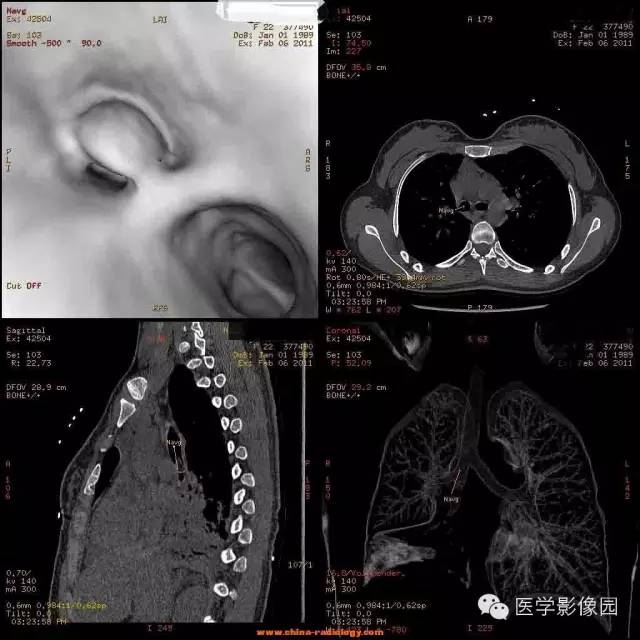

【病例】支气管异物1例CT影像表现

女,22岁,食用开心果后咳嗽不适。

管支气管异物是临床常见急症。异物可存留在喉咽腔、喉腔、气管和支气管内,引起声嘶、呼吸困难等,右支气管较粗短长,故异物易落入右主支气管。75%发生于2岁以下的儿童。CT三维重建清晰直观的显示异物的大小、位置,并能观察肺组织内是否有病变。